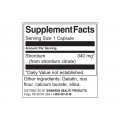

Дозировка: 1 капсула

Дози в опаковка: 60

| Състав в 1 доза (1 капсула) | Стойност | %ПДД |

| Стронций (от стронциев цитрат) | 340 мг | ** |

† Дневните дози са базирани на 2000 калории.

** Daily Value не е установено.

Други съставки: желатин, оризово брашно, калциев лаурат, силициев диоксид.